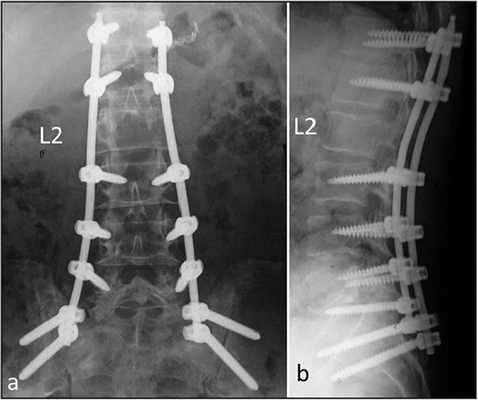

- Транспедикулярная фиксация – эта тактика подразумевает установку в смежные тела позвонков через педикулу (ножки) корригирующей металлоконструкции, представляющей собой винты, которые жестко соединяются между собой специальными штангами. Назначаются подобные манипуляции при переломах и смещениях позвонков, выраженных прогрессирующих сколиозах и стенозах позвоночника.

Транспедикулярная фиксация при сколиозе.

Задняя стабилизация позвоночника выполняется с помощью транспедикулярного фиксатора, усиленного при необходимости ляминарными крючками. Операционная рана ушивается послойно. Активный аспирационный дренаж удаляют через 1-2 дня после операции при объеме отделяемого менее 50 мл за смену. Мобилизуют пациентов как можно раньше и в условиях дополнительной наружной фиксации грудопоясничным корсетом, который рекомендуется использовать еще в течение последующих трех месяцев. В течение всего срока наблюдения за пациентами периодически проводят контрольную рентгенографию. Клинический пример использования описанной методики представлен на рисунке ниже.